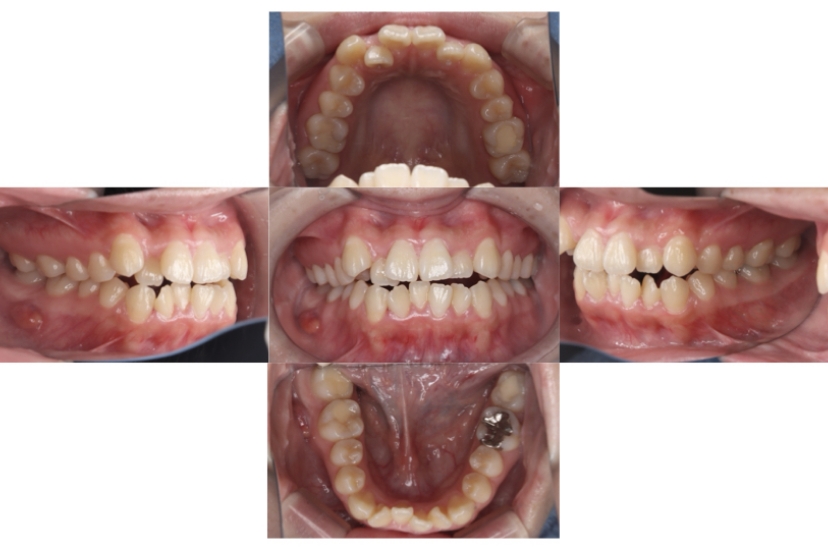

症例1

上顎前突、叢生

抜歯

ブラケット矯正

上下顎叢生、上顎前突(出っ歯、上下の前歯のガタガタ)のケースです。

装置はラビアル(上下表側)で、上顎の小臼歯を2本抜歯を行っています。抜歯したスペースを使って、上の前歯の後方移動と叢生(ガタガタ)と出っ歯の改善を行っています。下は歯と歯の間にIPR(隣接面削合)を行い、スペースを確保し、叢生の改善を行っています。

主訴 前歯のガタガタと出っ歯が気になる。

年齢・性別 47歳 女性

お住まいの地域 神奈川県川崎市

治療方針 抜歯スペースおよびIPRを利用して上前歯の叢生(ガタガタ)の改善

抜歯部位 上顎左右第一小臼歯

使用装置 ラビアル(上下表側)、顎間ゴム

治療期間 2年0か月

治療回数 15回

リテーナー クリアリテーナー

AFTER